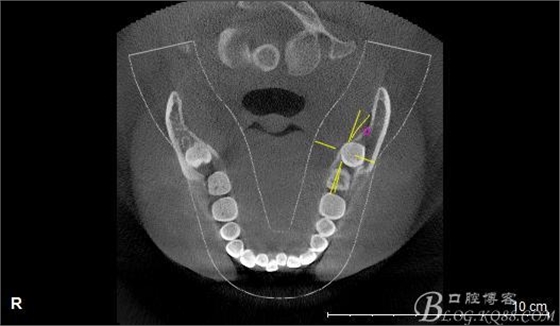

口內(nèi):38未萌出。37遠(yuǎn)中牙周袋10mm,CT:38牙冠倒置。牙齦紅腫,捫診可有少量血性滲出,無波動(dòng)感。印象診斷:38冠周炎。處理:1.抗炎治療,改善張口度。2.炎癥消退后,拔除38.

一、術(shù)前CBCT影像資料